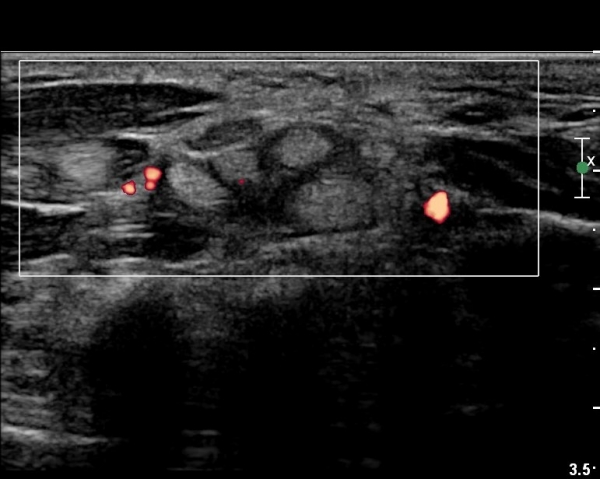

µµÇ÷¯°Ë»ç¿¡¼­ Ç÷·ùÁõ°¡°¡ °üÂûµÈ´Ù(»çÁø 2).